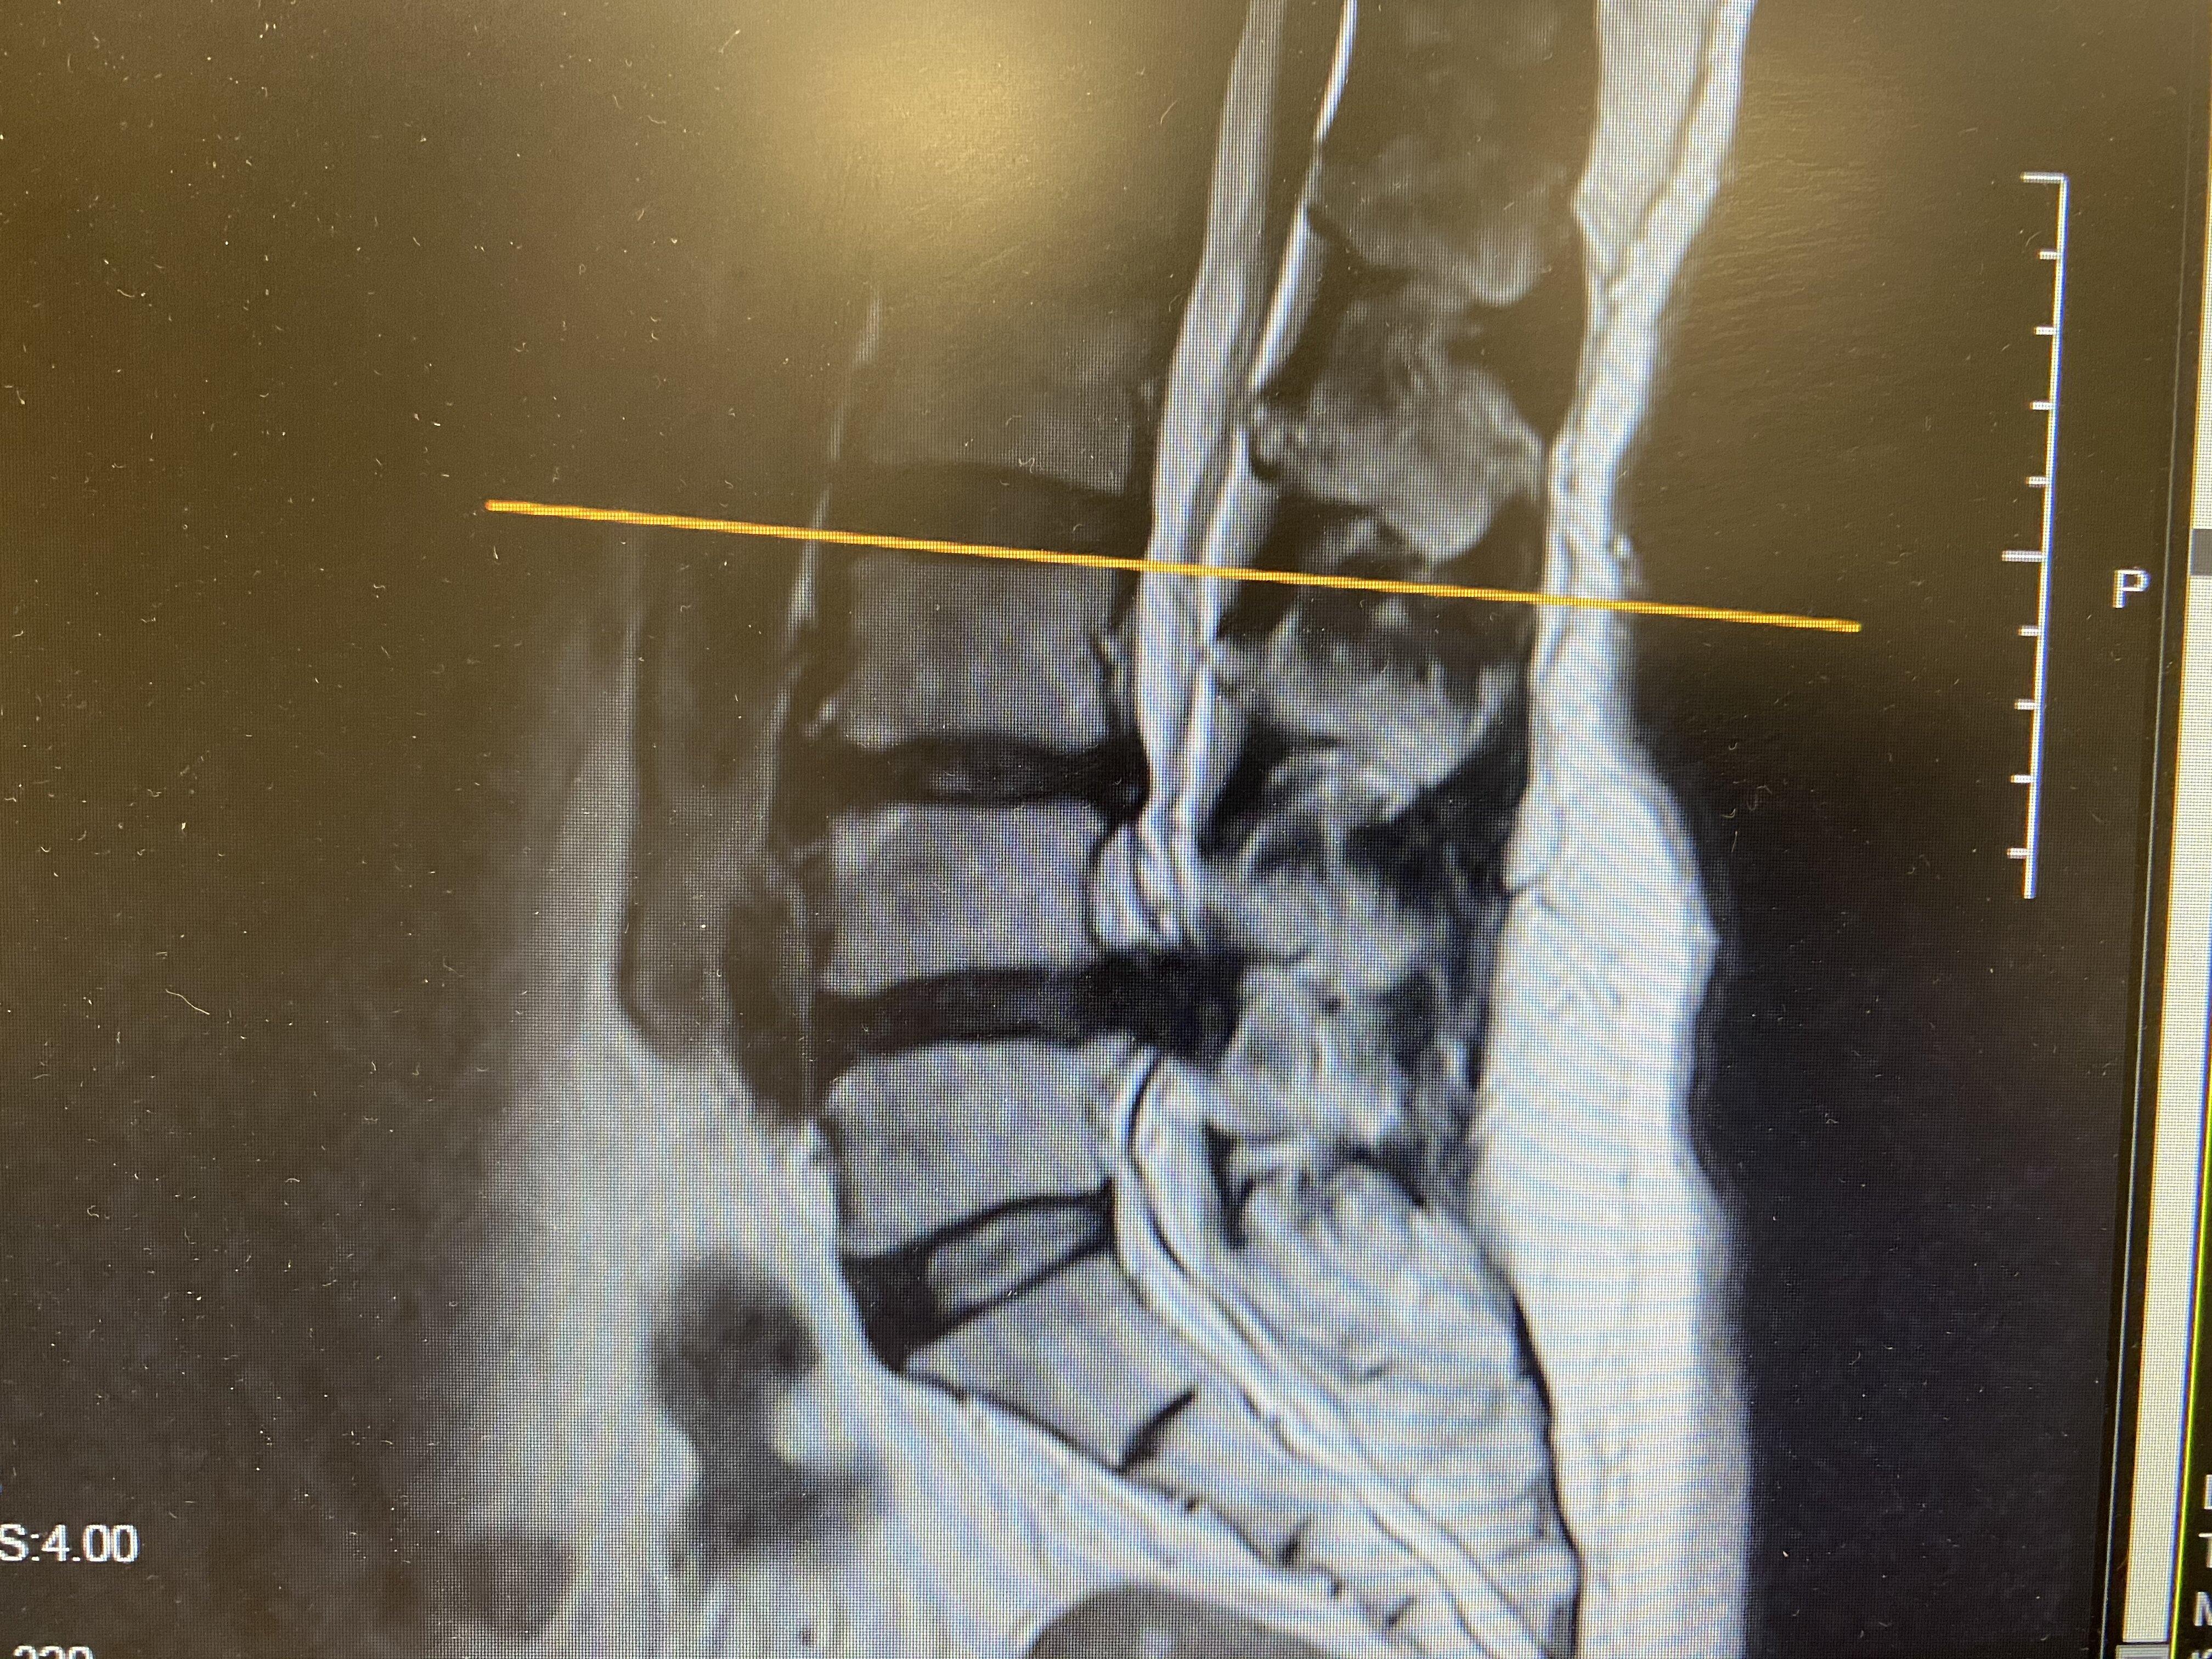

腰椎间盘突出症(Lumbar disc herniation,LDH)非常普遍,几乎每个人的一生中都会有不同程度的腰椎间盘问题。其主要是腰椎椎间盘各部分(髓核、纤维环、软骨板),尤其是髓核,本身有不同程度的退行性改变后,在外力因素的持续或反复作用下,椎间盘的纤维环破裂,髓核组织从破裂处突出(或脱出)于后方椎管内,导致相邻马尾神经根遭受刺激或压迫,而产生一系列腰痛、一侧下肢或双下肢麻木疼痛、甚至大小便障碍、性功能障碍等临床症状体征,称之为腰椎间盘突出症。

不同腰椎节段突出,引起不同腰腿部区域的临床症状,腰椎间盘突出症以L4-5、L5-S1发病率最高,大约占95%。